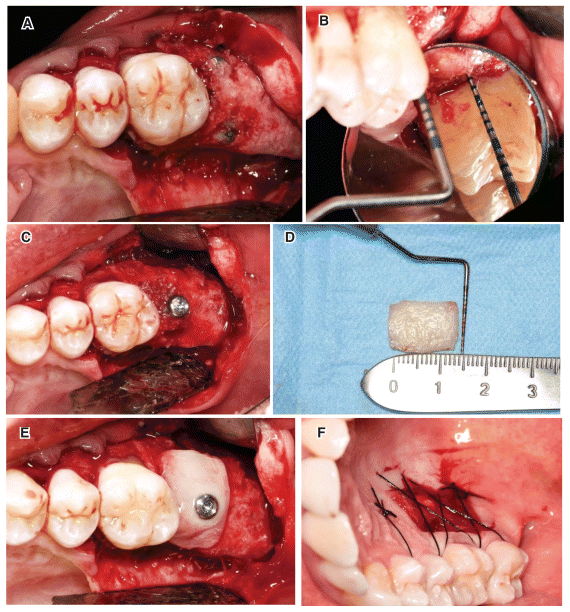

The patient underwent a complete oral hygiene session one week before surgery. On the day of surgery, he was instructed to rinse his mouth with chlorhexidine digluconate (0.20%) for 1 minute after verifying a full mouth plaque score of <20%. Local anesthesia was performed with 4% articaine (1:100,000 epinephrine). A crestal incision was made in the area of tooth 27, slightly toward the vestibular side, and continued in the sulcus of the two neighboring teeth; the incision ended with a vertical hockey-stick Releasing the cut for better access.11 A full-thickness flap was raised on the buccal side. No releasing incisions were made on the palatal side, and the supracrestal soft tissue was tunnel-cut in the area corresponding to the defect (Fig. 2a). The buccal flap was subsequently released in a disto-mesial direction. Direction exposing the underlying connective tissue with a single, continuous incision of the periosteum using a scalpel with a 15c blade. The tissue was stretched using a brushing technique, allowing significant coronal advancement of the flap.12 A millimeter probe was used to measure the periodontal defect at the root portion of tooth 26, calculated from the residual bone plane to the cemento-enamel junction (CEJ) of the tooth, yielding a measurement of 9 mm (Fig. 2b–2c). The vertical GBR technique was performed during the first operation using a titanium-reinforced dense-polytetrafluoroethylene (d-PTFE) membrane (Cytoplast. TI250XL, Osteogenics Biomedical Inc., Lubbock, TX, USA) and a graft made from a high-porosity biomaterial mixture of porcine-derived carbonate apatite (Zcore®, Osteogenics Biomedical Inc., Lubbock, TX, USA) and autologous bone harvested from the left external oblique line of the mandible (mixed in a 1:1 ratio). Bone sampling was performed through a single bucco-lingualincision (approximately 2 cm), creating a subperiosteal mucosal tunnel with a distal extension from the access incision. The bone particulate was collected and stored using a bone scraper (Micross, Meta Technologies, Reggio Emilia, IT) designed for tunnel techniques (Fig. 2d–2e).13,14 Before proceeding with the GBR of the edentulous site, a periodontal regenerative procedure was performed on the distal root of tooth 26. The procedure involved curettage of the extra osseous root portion, application of ethylenediaminetetraacetic acid (EDTA; Prefgel, Straumann, Basel, Switzerland) for 2 min, and placement of a layer of enamel matrix derivative (EMD; Emdogain, Straumann (Basel, Switzerland), according to the guidelines for regenerating periodontal intrabony defects established by the American Association of Periodontology15 and the European Federation of Periodontology of 2020.16. After treatment with EMD, a second thin layer of pure autologous The bone was placed on the root portion. Following multiple perforations of the cortical bone, two 9-mm tenting screws were inserted at the edentulous site (Fig. 2f). The allograft was positioned, and the membrane was adapted and secured with 3-mm self-drilling screws on the buccal and palatal sides (Profix™, Osteogenics Biomedical Inc., Lubbock, TX, USA). The membrane screws on the palatine side were inserted using a transmucosal technique to minimize excessive detachment of the palatine mucosal tissue (Fig. 2g). The margin of the membrane was modeled to remain 1–2 mm away from the natural tooth; the gap was covered with collagen membrane (Bio Gide, Geistlich Pharma AG, Wolhusen, Switzerland). The coronally displaced flap was tested for passivity and sutured with a triple-layer suture using force-breaking stitches and employing a monofilament polyglycolic acid (PGA) suture thread (Serafast, Serag-Wiessner, Naila, Germany).17 The patient was prescribed amoxicillin/clavulanate potassium (875 + 125 mg) tablets (Augmentin, GlaxoSmithKline, Brentford, UK) for a week, one tablet to be taken every 8 hours, and Toradol (20mg/ml; Recordati, Milan, Italy), 10 drops sublingually twice a day for 1 week. The patient was also instructed to spray a 0.5% chlorhexidine solution three times a day and to avoid mechanical plaque removal in the surgical area until the sutures were removed. The sutures were removed 2 weeks after surgery, and post surgical visits were scheduled weekly for the first 3 weeks to monitor healing and verify wound closure during the postoperative period.